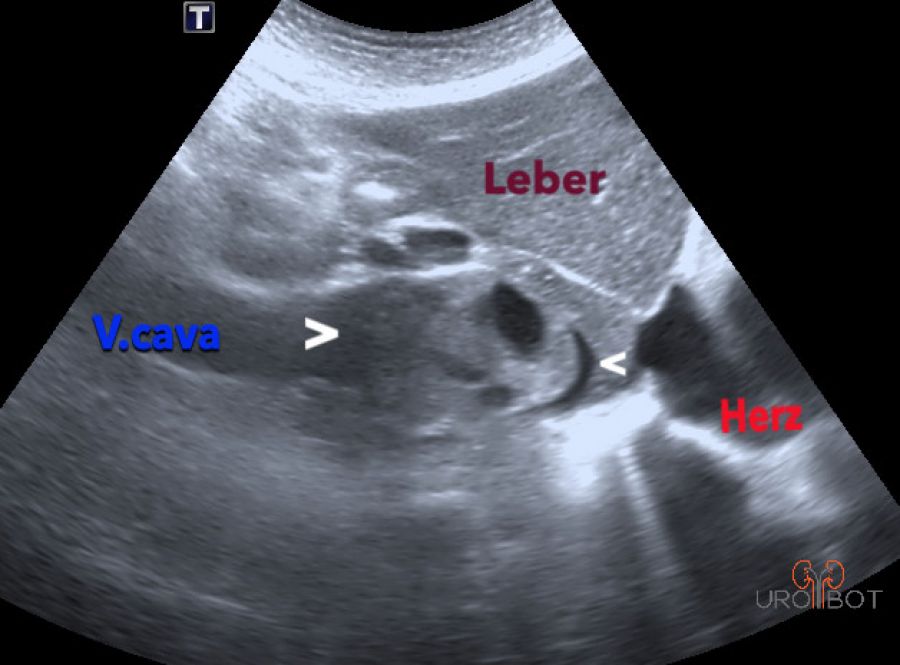

Das Video zeigt eine sonographische Untersuchung der rechen Seite mit Nachweis eines großen Tumorthrombus in der unteren Hohlvene.